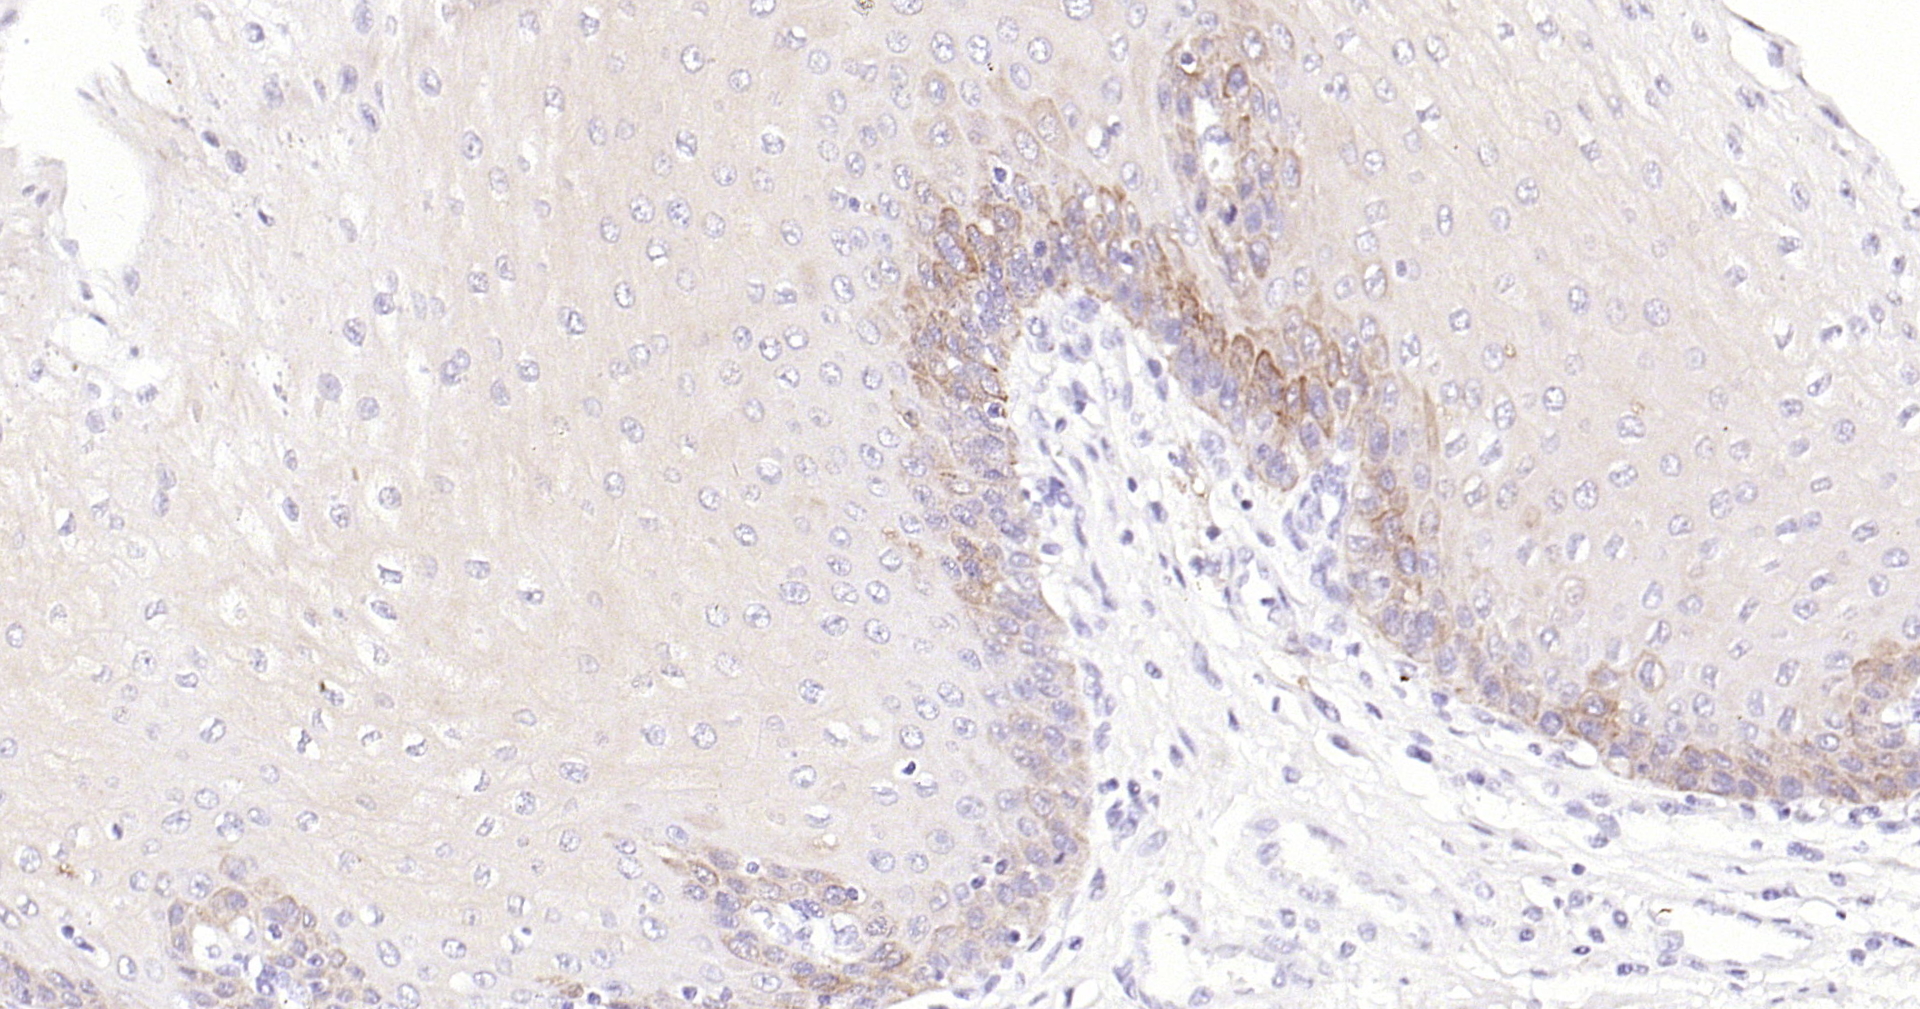

• IHC-P

IHC-P IHC-P1:100-500